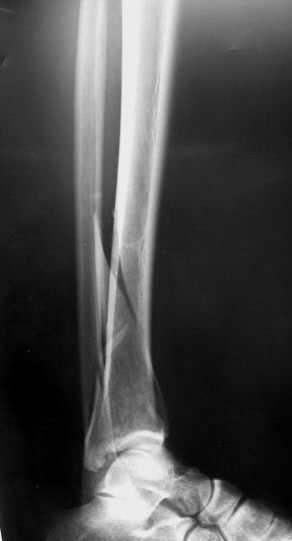

Пример - довольно похожий перелом, оперированный в первые 8 часов после аварии у 40-летнего больного, страдающего тяжёлым сахарным диабетом 1 типа.

На мой взгляд оптимальным для такого перелома является аппарат Илизарова, который позволяет:

1. Возможность раннего дефинитивного лечения.

2. Возможность в некоторых случаях закрытой репозиции

3. Ранняя разработка сустава в аппарате

4. Частичная нагрузка с первых дней после операции

5. Сравнительно быстрое сращение - 3 месяца.

6. Снижение сроков реабилитации.